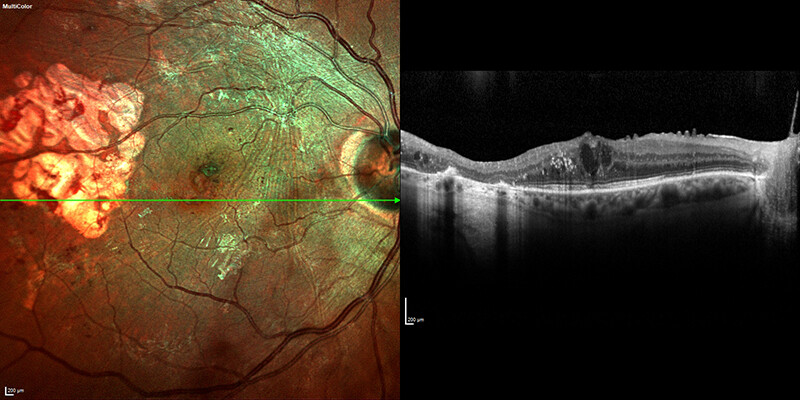

OCT imaging reveals an epiretinal membrane

Image courtesy: Farrell Tyson, MD